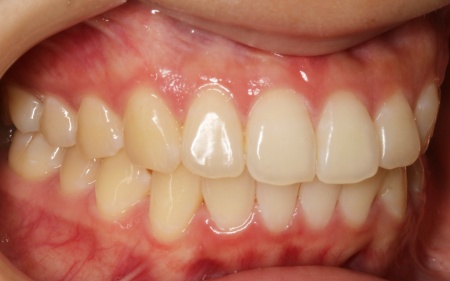

20代女性 乱れた上下の歯並びをハイブリッド矯正で改善した症例

拝見したところ、上下の歯はデコボコに生えている状態でした。

このままでは見た目が気になるだけでなく、磨き残しが起こりやすくなることで虫歯や歯周病などの発症リスクが高まります。